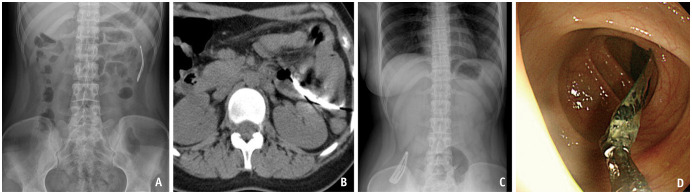

异物摄入和感觉是常见的临床情况遇到急诊和门诊设置。真正的异物摄入通常包括吞咽异物的历史,通常通过x线检查证实。异物摄入的处理取决于异物的类型、大小和位置,以及患者的症状。高风险物体,如钮扣/盘状电池、多个磁铁和尖锐物体,通常需要紧急或紧急内镜切除,以防止穿孔、阻塞和瘘管形成等严重并发症。影像学对诊断和治疗至关重要,x线片是一线方式,CT在检测放射性物体和并发症方面具有卓越的灵敏度。即使没有实际的异物存在,异物摄入和感觉的模拟者也会出现在运动障碍(如贲门失弛缓症)、结构或粘膜异常(如Zenker憩室、反流性食管炎和食管狭窄)和外源性压迫。虽然这些模仿者产生相似的症状,但它们需要不同的诊断方法。本文综述了各种异物的影像学表现、处理策略以及其模仿物的特征,强调了及时准确区分的重要性,以指导适当的干预和改善患者的预后。

Foreign body ingestion and sensation are common clinical conditions encountered in emergency and outpatient settings. True foreign body ingestion typically involves a history of swallowing a foreign object and is often confirmed by radiographic findings. The management of foreign body ingestion depends on the type, size, and location of the object, as well as the patient's symptoms. High-risk objects, such as button/disk batteries, multiple magnets, and sharp objects, often require urgent or emergent endoscopic removal to prevent severe complications such as perforation, obstruction, and fistula formation. Imaging is crucial for diagnosis and management, with radiographs being the first-line modality and CT offering superior sensitivity for detecting radiolucent objects and complications. Mimickers of foreign body ingestion and sensations, even without the presence of an actual foreign body, arise from motility disorders (e.g., achalasia), structural or mucosal abnormalities (e.g., Zenker's diverticulum, reflux esophagitis, and esophageal strictures), and extrinsic compression. Although these mimickers produce similar symptoms, they require different diagnostic approaches. This review highlights the radiological findings, management strategies for various foreign bodies, and the distinguishing features of their mimickers, emphasizing the importance of timely and accurate differentiation to guide appropriate interventions and improve patient outcomes.